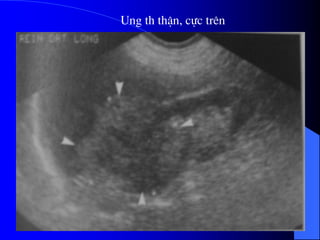

- Siãu ám phán biãût âæåüc khäúi âàûc vaì dëch.

Nãúu laì khäúi âàûc seî xem xeït cáúu truïc ám, coï thãø

giaím, âäöng hoàûc tàng ám, xem âäü âäöng nháút ám,

väi hoïa.

Nãúu laì khäúi dëch, seî tçm täø chæïc âàûc hoàûc vaïch

trong nang.

Siãu ám coï thãø tháúy haûch di càn, xám láún ténh

maûch.

Noïi chung khi phaït hiãûn khäúi âàûc trãn siãu ám,

cáön chuûp CLVT âãø âaïnh giaï roî hån baín cháút, sæû

xám láún, di càn.